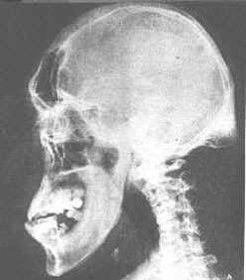

Symptoms: BMR is slow, body weight increases, mental activity slows so a person is less alert, skin becomes dry and puffy, hair becomes thin and brittle, thyroid gland may swell to form a goitre.... caused by what hormone and what condition